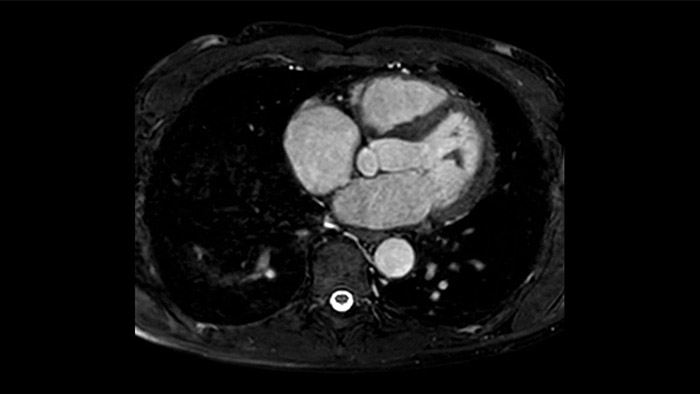

Diagnostic and prognostic utility of cardiac MR is increasing. Assess the anatomy and function of the heart using cine acquisitions, acquire information about perfusion and viability of the cardiac tissue, visualise potential edema with black blood sequence, access and even quantify tissue characterisation with CardiacQuant.

Pacemakers are not a hard contra-indication for CMR, there are many MR Conditional pacemakers. ScanWise Implant3 offers step-by-step guidance to enter condition values of the implant manufacturer and automatically apply these values to the entire examination. Simplifying your scanning process for patients with MR Conditional implants.